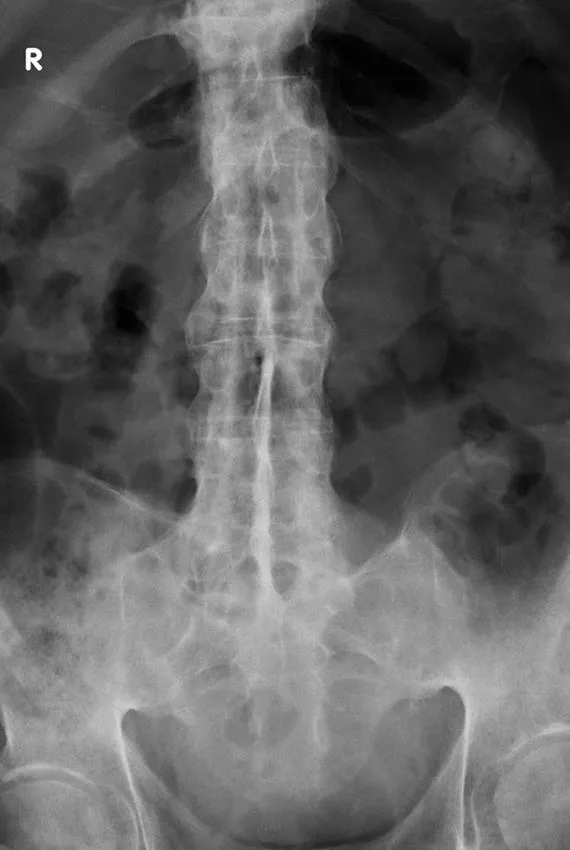

Age: 72 years | Gender: Male |

Clinical problem: Back pain following a fall | |

Images in exam case: Plain radiograph (4), CT (2) | |

FINDINGS

- 1. X-ray thoracolumbar spine:

- a. Marginal syndesmophytes

- b. Ossification of the interspinous ligament – ‘dagger’ sign

- c. Ossification of the anterior longitudinal ligament

- d. Fusion of both sacroiliac joints

- e. Fracture through mid-thoracic intervertebral disc with retrolisthesis of superior vertebra.

- 2. CT whole spine:

- a. Ossification of anterior longitudinal ligament

- b. Fusion of multiple facet joints

- c. Severe cervicothoracic kyphosis

- d. Fracture line starting at D5/6 intervertebral disc and extending into the posterosuperior body of D6 and D6/7 facet joints

- e. Mild retrolisthesis of D5 over D6

- f. Widened lucent line through D10/11 disc space and facet joints with adjacent reactive sclerosis

- g. Distended urinary bladder.

DIAGNOSIS

- 1. Ankylosing spondylitis, acute fracture through D5/6 extending through the posterior elements. This is an unstable fracture as all three vertebral columns are disrupted.

- 2. Pseudoarthrosis D10/11, most likely secondary to non-union of an old fracture.

Ankylosing spondylitis is a regular feature of the FRCR 2B examination, either as a written case or in the viva. The scenarios involved could be bilateral symmetrical sacroiliac joint erosion, sclerosis or fusion, erosion of the anterosuperior corner of the vertebra on lateral radiograph (Romanus sign), sclerosis of the anterosuperior corner and periostitis of the waist giving rise to vertebral ‘squaring’, syndesmophyte formation leading to ‘bamboo spine’, intervertebral disc calcification, ossification of the anterior longitudinal, posterior longitudinal, interspinous and supraspinous ligaments, kyphosis and facet joint fusion. Other skeletal features include erosions of the symphysis pubis and ischial tuberosities, asymmetrical erosive oligoarthritis, atlanto-axial dislocation and osteoporosis. In a traumatic setting, the fracture line may run through the intervertebral disc space right through into the posterior elements, and may be missed if one is not vigilant. Clinically occult fractures can also occur, leading to mobile non-union (pseudoarthrosis) – the so-called Anderson lesion.